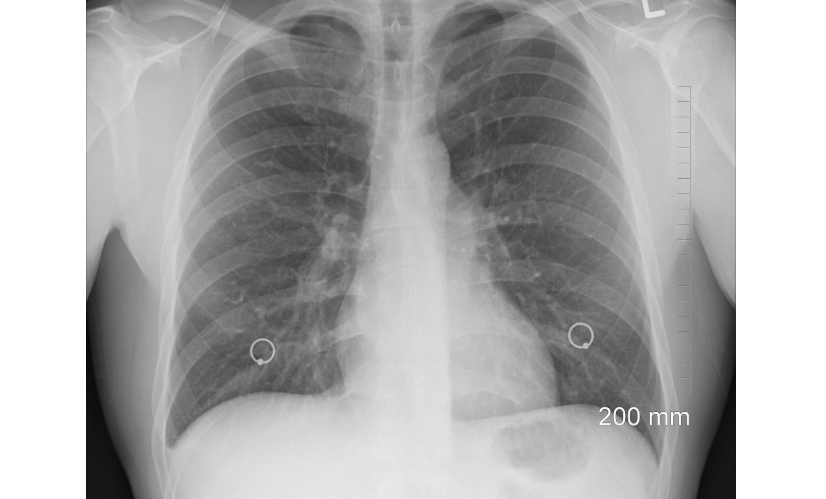

2. 영상검사(X-ray, MRI, CT)

- 늑골 골절, 척추질환, 종양, 디스크 병변 여부를 확인합니다.